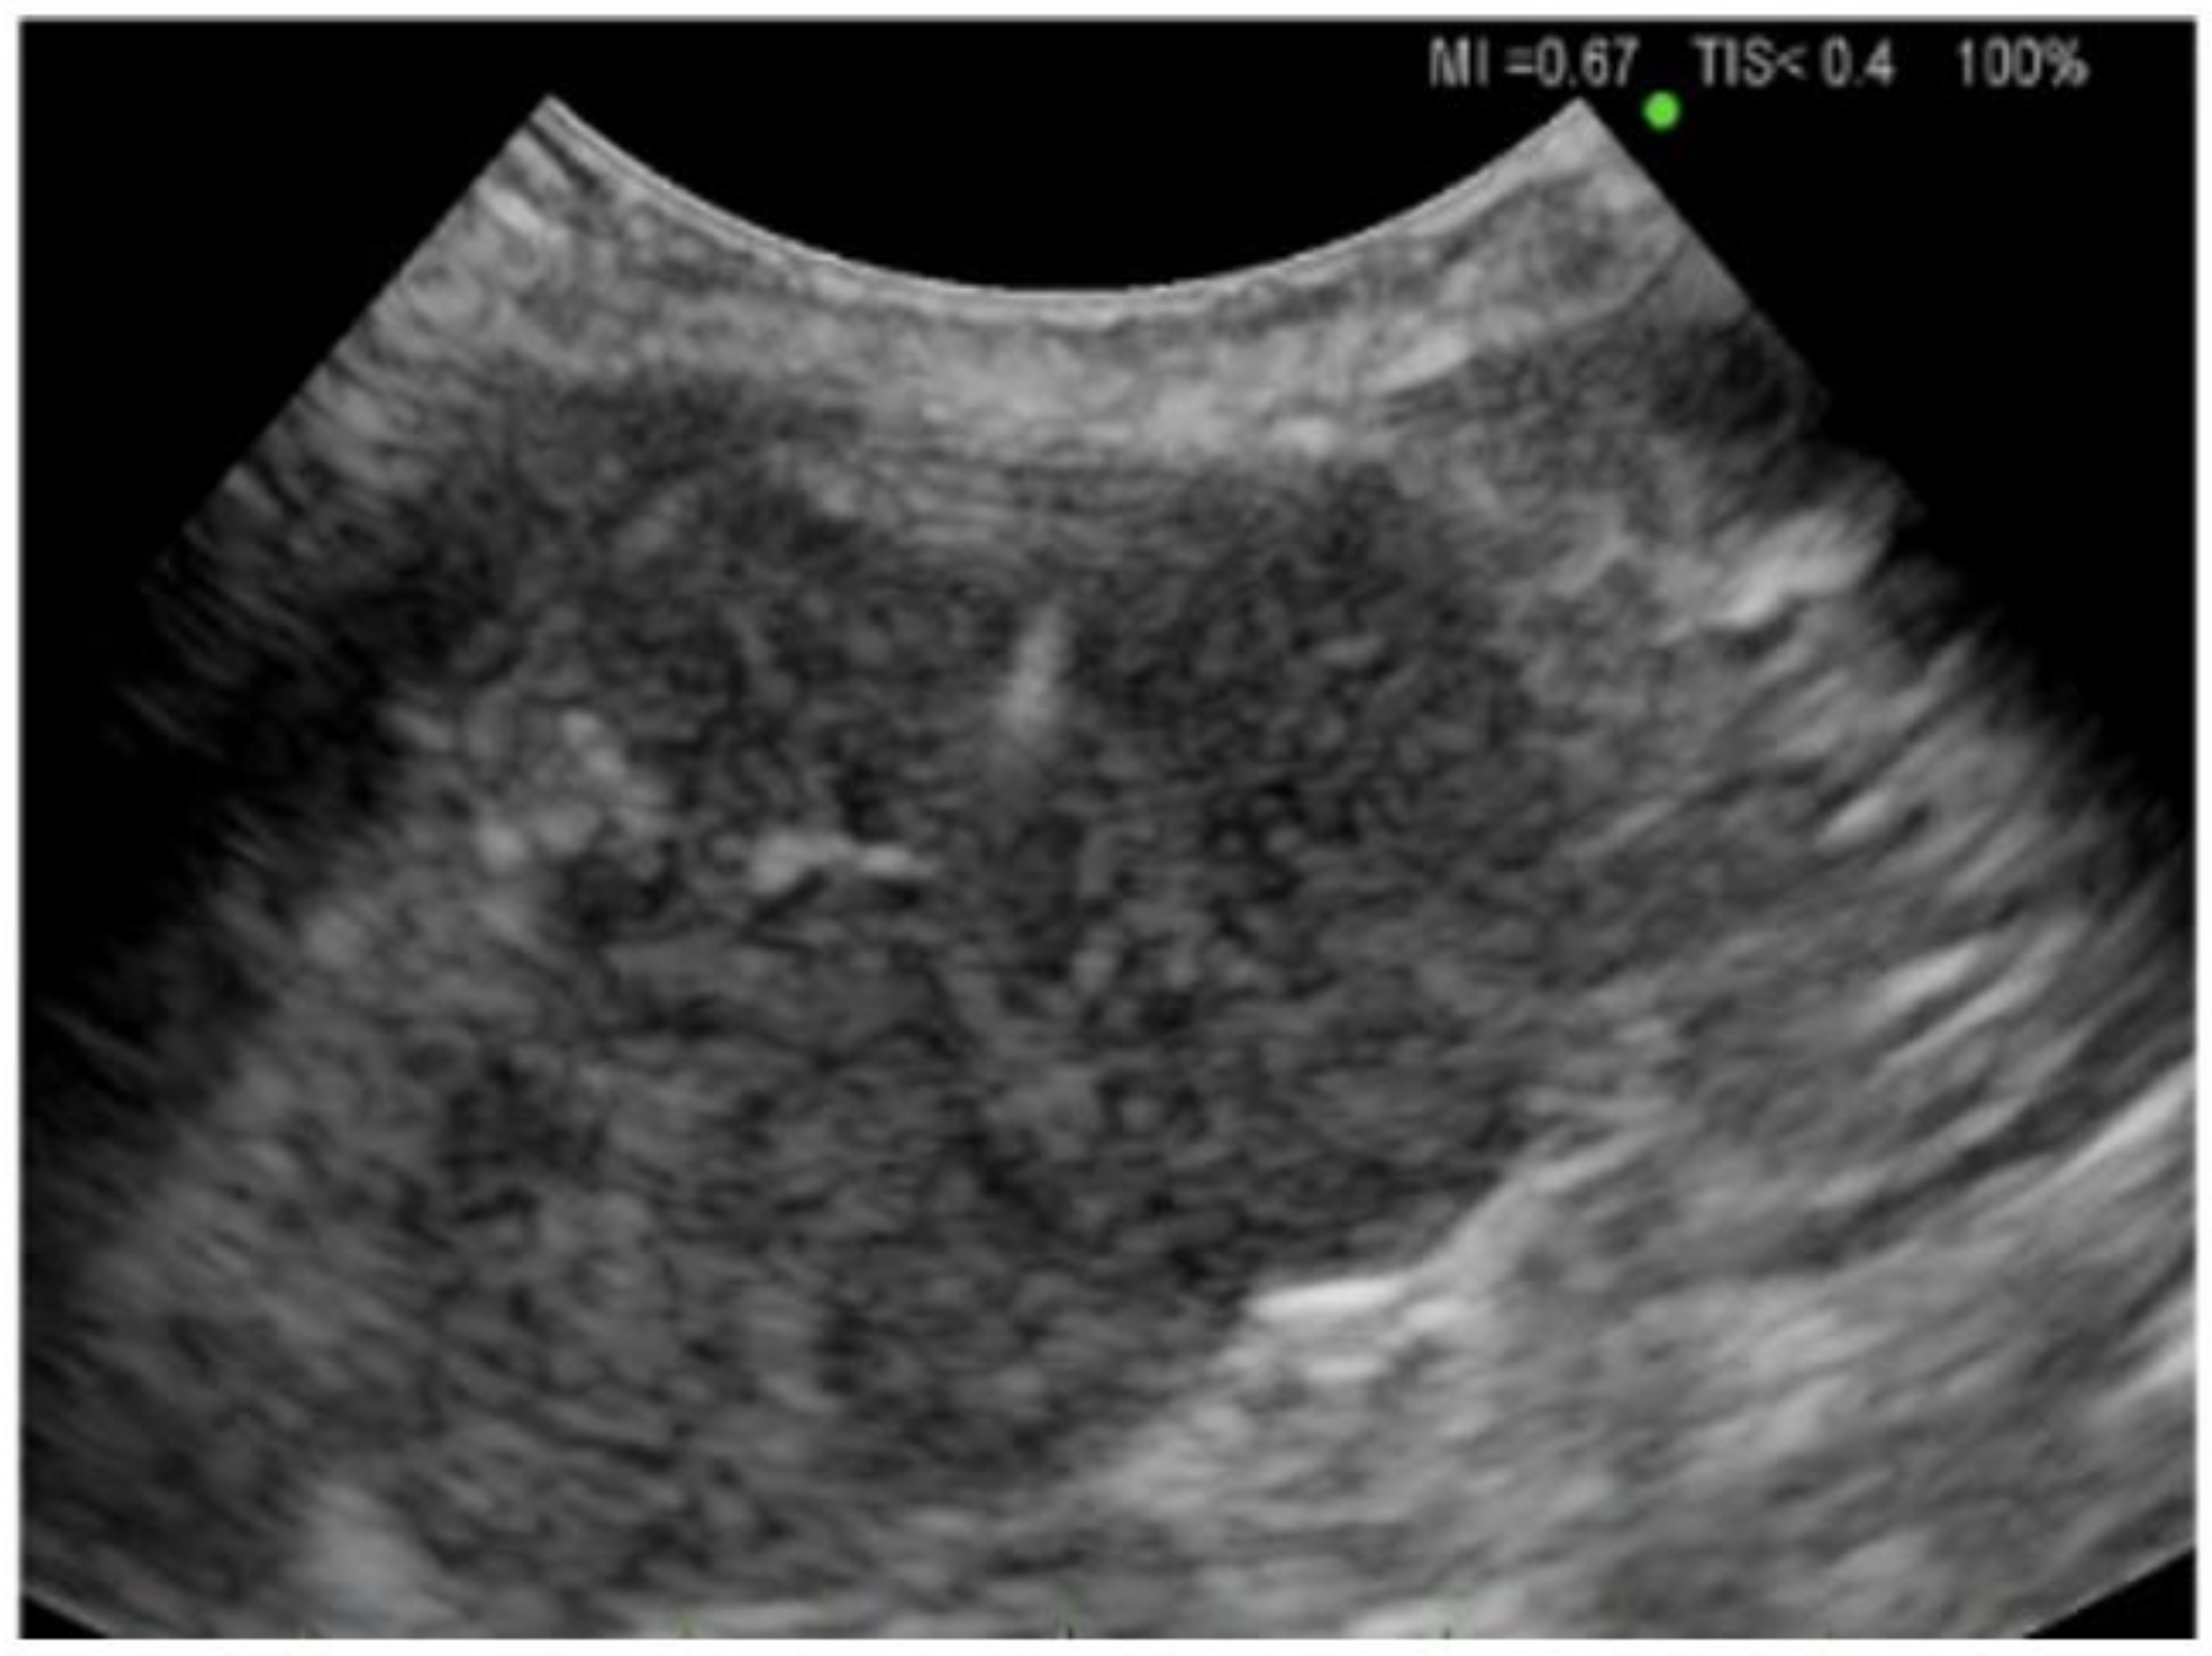

2.3. Thoracic Ultrasound